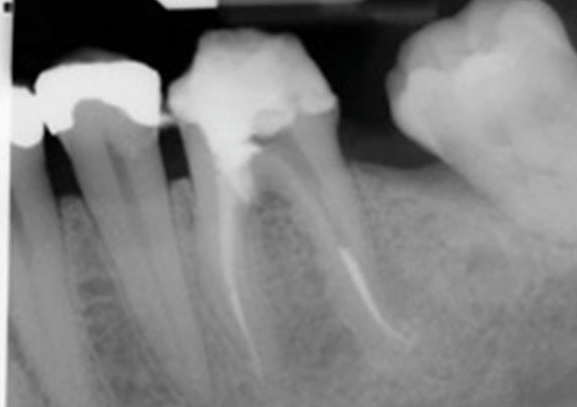

(1.) Preoperative radiograph of teeth Nos. 30 and 31 exhibiting previously treated, symptomatic apical periodontitis and pulp necrosis with a chronic apical abscess and an endodontic-periodontic lesion, respectively.

Figure 1

(2.) Postoperative radiograph after the performance of nonsurgical root canal re-treatment on tooth No. 30 and root canal therapy with hydraulic condensation and bioceramic sealer on both teeth followed by amalgam core buildups. (Case courtesy of David Tran, DMD, Advanced Graduate Program in Endodontics, Harvard School of Dental Medicine).

Figure 2